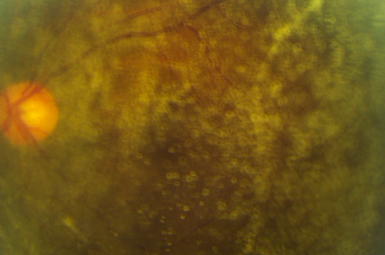

Intermediate Uveitis

Intermediate Uveitis occurs when inflammation involves only the vitreous. Causes include Pars Planitis, and numerous infectious and inflammatory etiologies.

Posterior Uveitis

This represents Chorioretinal inflammation. It is caused by numerous types of infection and inflammation, and frequently requires medical therapy.